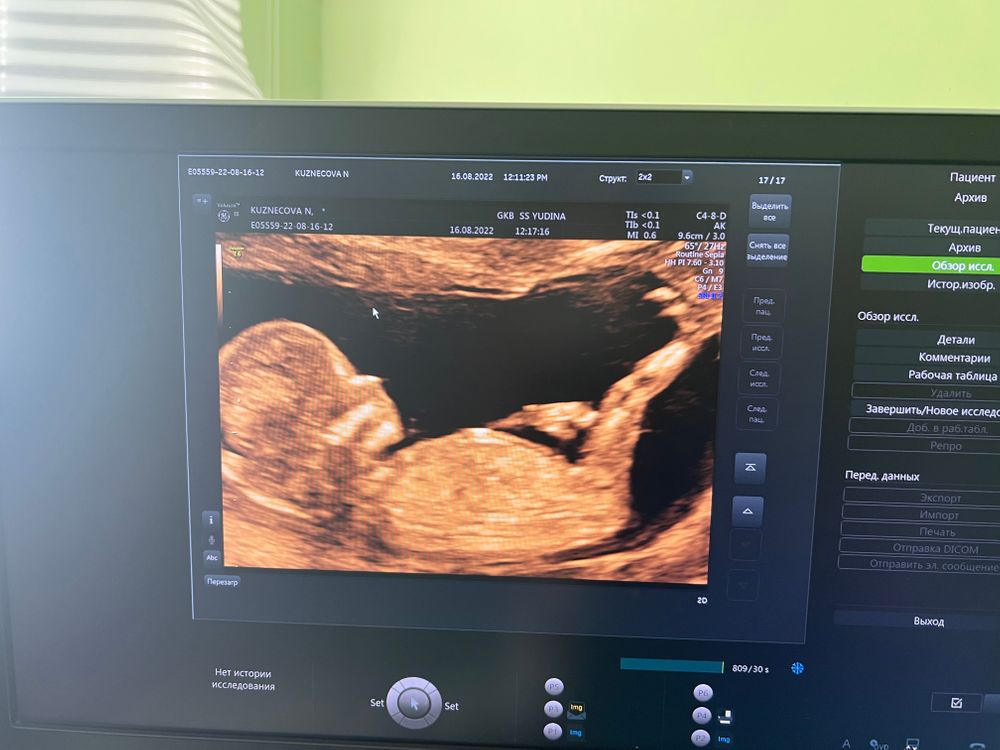

Первый волнительный скрининг)

На 1ом скрининге тоже плацента перекрывала внутренний зев, в 14 недель делала узи , уже нормально все было, поднялась и по передней стенке. В большинстве случаев плацента поднимается. По 1ому скринингу судить не стоит, не переживайте)

пс му -по передней стенке миоматозные узлы

Моя боль. 1 скрининг. Неимунная водянка плода. ТВП 5,5 Результаты биопсии плаценты после родов